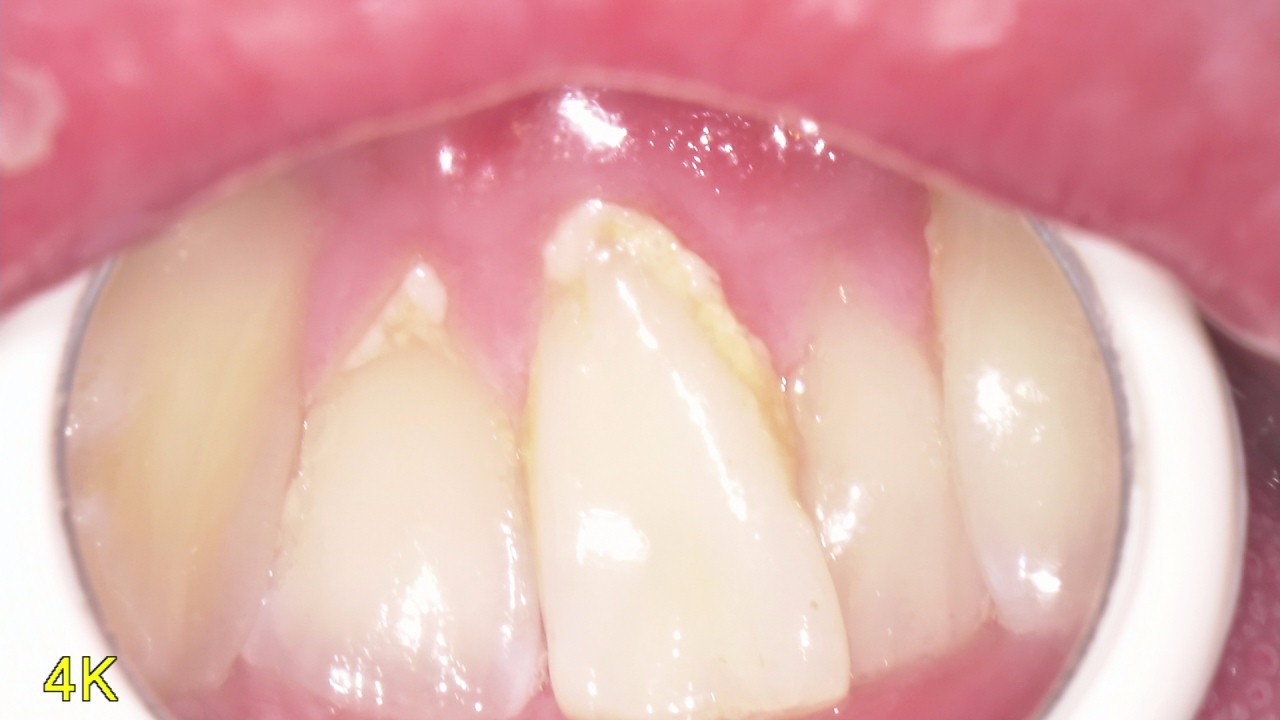

歯の破折の治療

歯の破折って聞いたことありますか? 骨が折れることを骨折といいますが歯が折れる、割れることももちろんあるんです。 今回の写真は他院で歯が痛くて治療したけど違和感や噛んで痛いのが治らないということで来院されました。 口腔内 […]